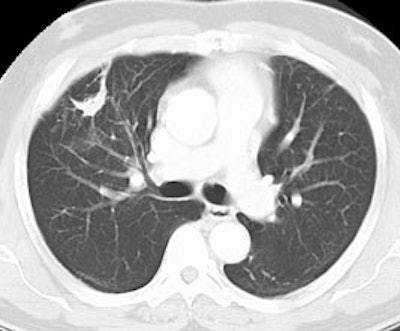

False positive Neotect exam: CT scan demonstrated an irregular nodule within the right middle lobe. Transaxial Neotect image demonstrated abnormal tracer accumulation in the lesion. The lesion was surgically resected and found to be related to fibrosis and chronic inflammation. Although very sensitive, the Neotect exam does suffer from a lower specificity and the potential for false positive exams. Case courtesy Dr. Jamie Montilla. |